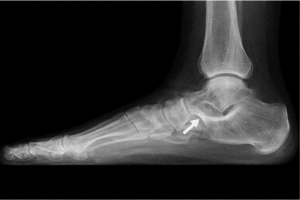

Síndrome del seno del tarso: Dolor crónico en la parte lateral del tobillo y pie, en una cavidad llamada seno del tarso. Un arco caído y pie pronado hacen que las estructuras en esa zona (que están muy bien vascularizas e inervadas) se compriman constantemente entre los huesos del pie. La persona puede sentir dolor difuso en el empeine o lateral del tobillo, especialmente al caminar en terrenos irregulares.